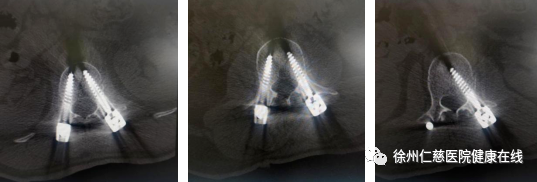

术后复查

“腰椎置钉若位置不准,会影响脊柱稳定性,甚至伤及神经,给患者带来后遗症。和传统手术相比,“天玑”骨科手术机器人辅助手术切口小、定位精准、患者疼痛轻、恢复快。”孟磊副主任医师说道。